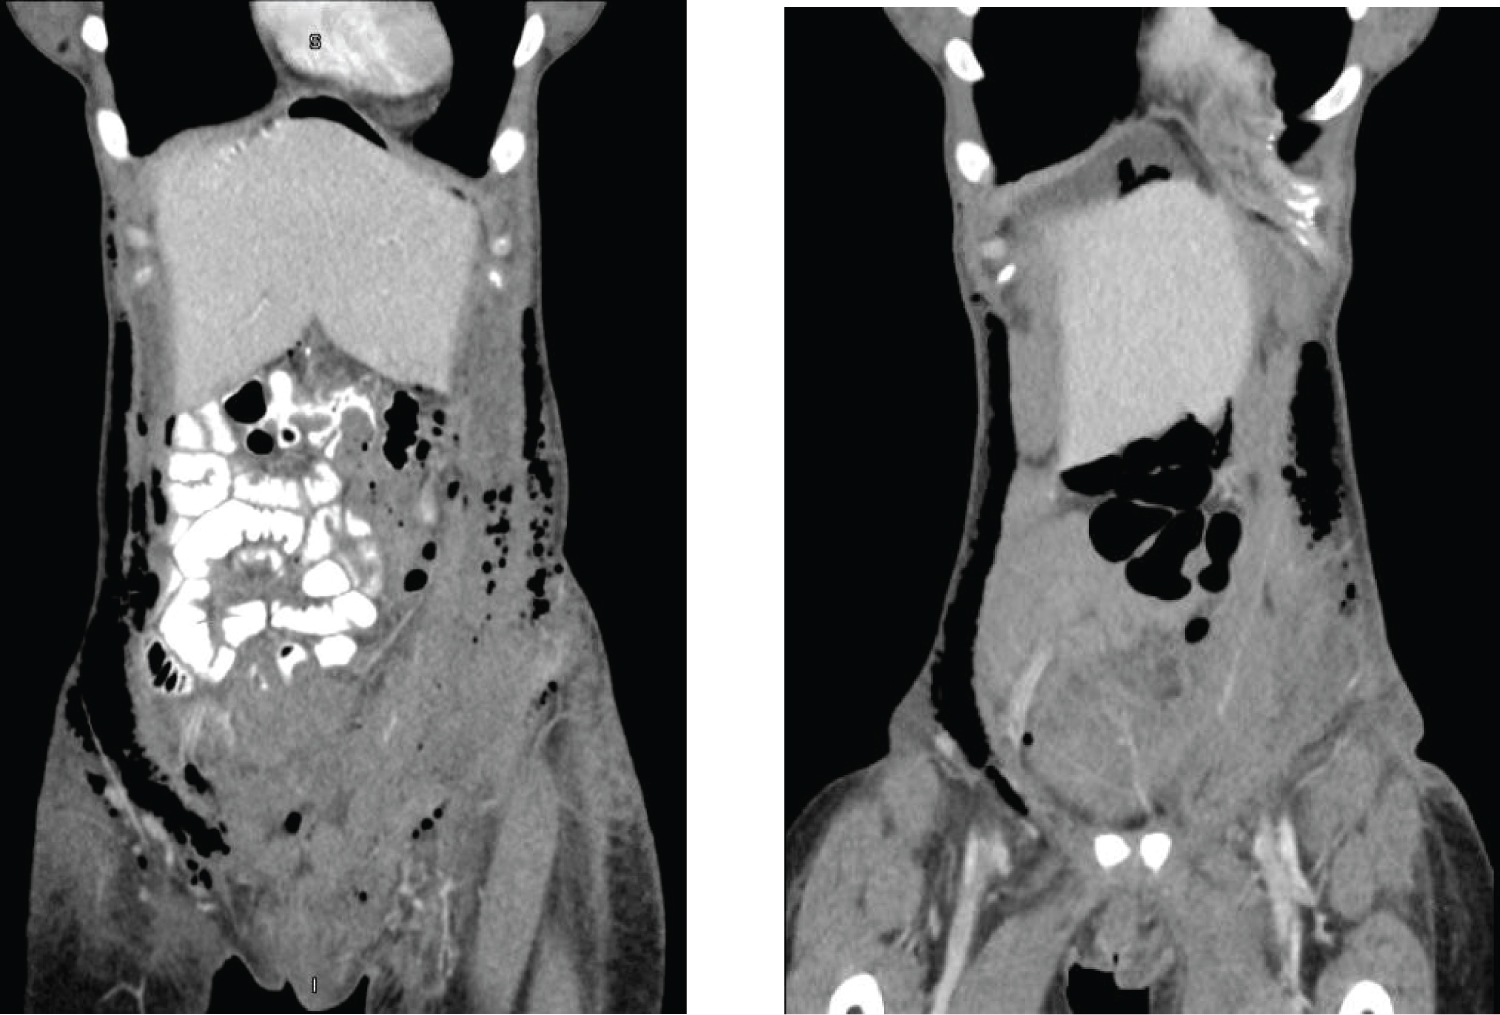

Postoperatively, the patient was symptomatically anemic and she was transfused 2 units of packed red blood cells with resolution of her symptoms. Her physical exam was notable for significant crepitus starting on postoperative day 2. The crepitus extended from her mons pubis to her xiphoid process and laterally to her flanks. The patient only reported mild bowel gas pain. Her abdominal exam was appropriately tender to palpation along her incision and otherwise soft without rebound or guarding. Her labs all trended normal with stabilization of her hemoglobin after transfusion. By postoperative day 3, the patient's subcutaneous emphysema persisted and though she passed flatus, she still had minimal oral intake. Computed tomography (CT) scan of the chest, abdomen, and pelvis confirmed subcutaneous air along the anterior abdominal and pelvic wall, but no pneumothorax, underlying abscess, or obvious bowel perforation (Figure 1, Figure 2 and Figure 3, left). Delayed CT imaging repeated several hours later showed progression of oral contrast through intact bowels, helping to rule out an underlying perforated viscus. The patient's oral intake normalized and meeting all postoperative milestones, she was discharged on postoperative day 5. She was readmitted on postoperative day 7 with abdominal pain and distension. Her abdominal crepitus had significantly decreased and repeat CT of the abdomen and pelvis demonstrated interval improvement of her subcutaneous emphysema (Figure 1, Figure 2 and Figure 3, right). She was discharged the next morning significantly improved with conservative management.

Figure 3: Subcutaneous emphysema (coronal view) on post-operative day 4 (left) vs. post-operative day 7 (right). View Figure 3